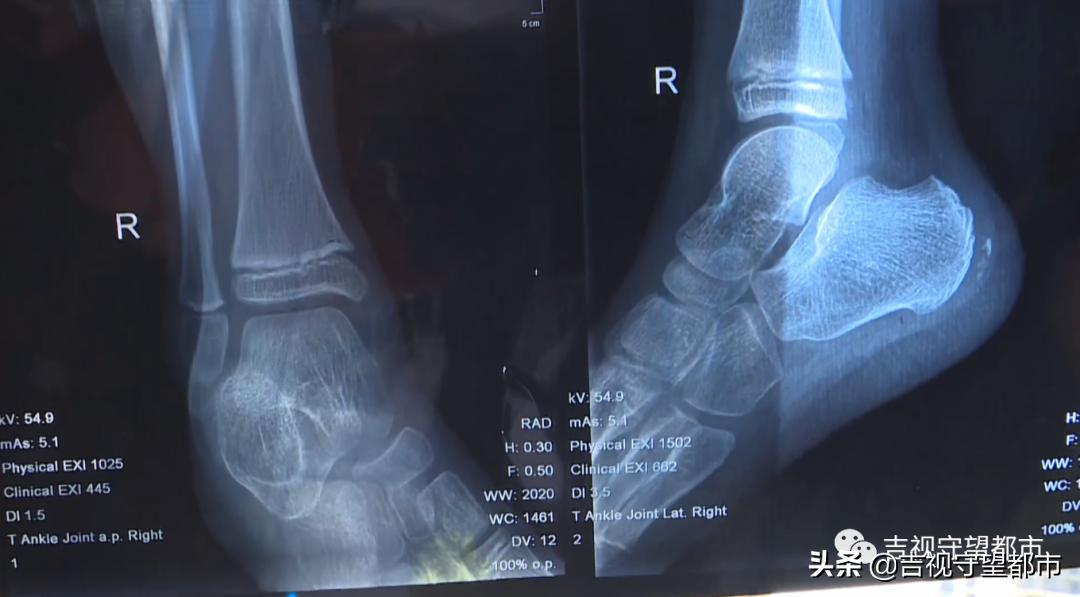

王女士告诉记者,女儿7岁,体验的攀岩项目是属于无保护措施的,当时有两名工作人员在孩子旁边进行指导。摔伤之后,女儿一直因为右脚疼痛而哭闹,随后,王女士和edong科学公园的工作人员一同带着孩子前往前进医院急诊就医。通过X光片,值班医院表示,孩子并无大碍。

这个医生细看说片子上有一个骨叉裂开了,他说你还是打上石膏吧,因为孩子小,晚上睡觉容易二次受伤,然后就给她打上石膏了。

视频中我们看到,女童右脚踝位置打上了石膏进行固定。